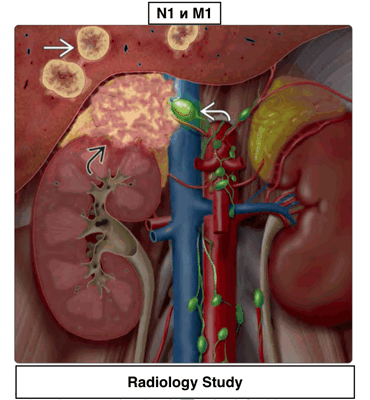

Стадирование рака надпочечников (TNM, AJCC).

- Nx - Регионарные лимфоузлы не могут быть оценены

- N0 - Регионарные лимфоузлы не поражены

- N1 - Метастазы в регионарные лимфоузлы

- M0 - Отдаленных метастазов нет

- M1 - Есть отдаленные метастазы

Пример N1 и M1 представлен в виде схемы на аксиальном срезе.